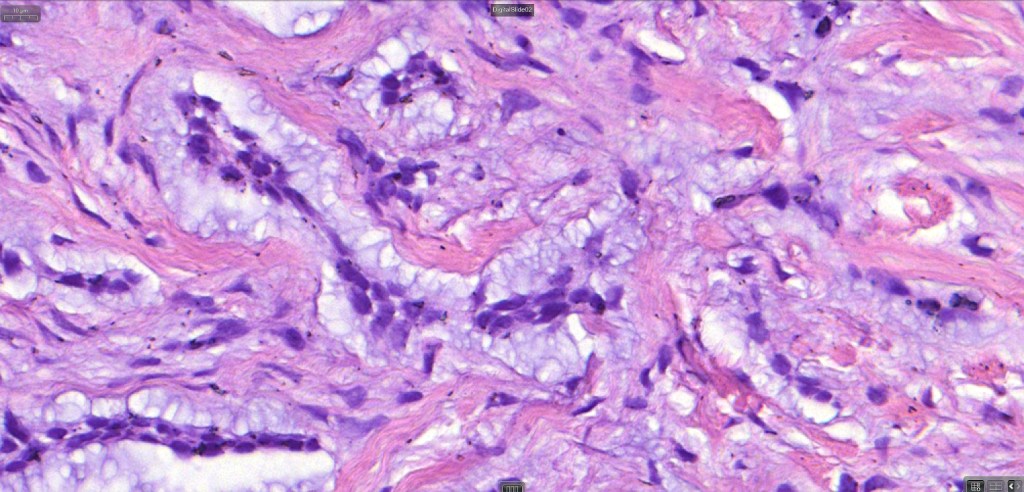

•The epithelial component is composed of uniform small, basophilic devoid of desmosomes

•Peripheral palisading

•Retraction artifact with stromal mucin

•Pseudoglandular appearance